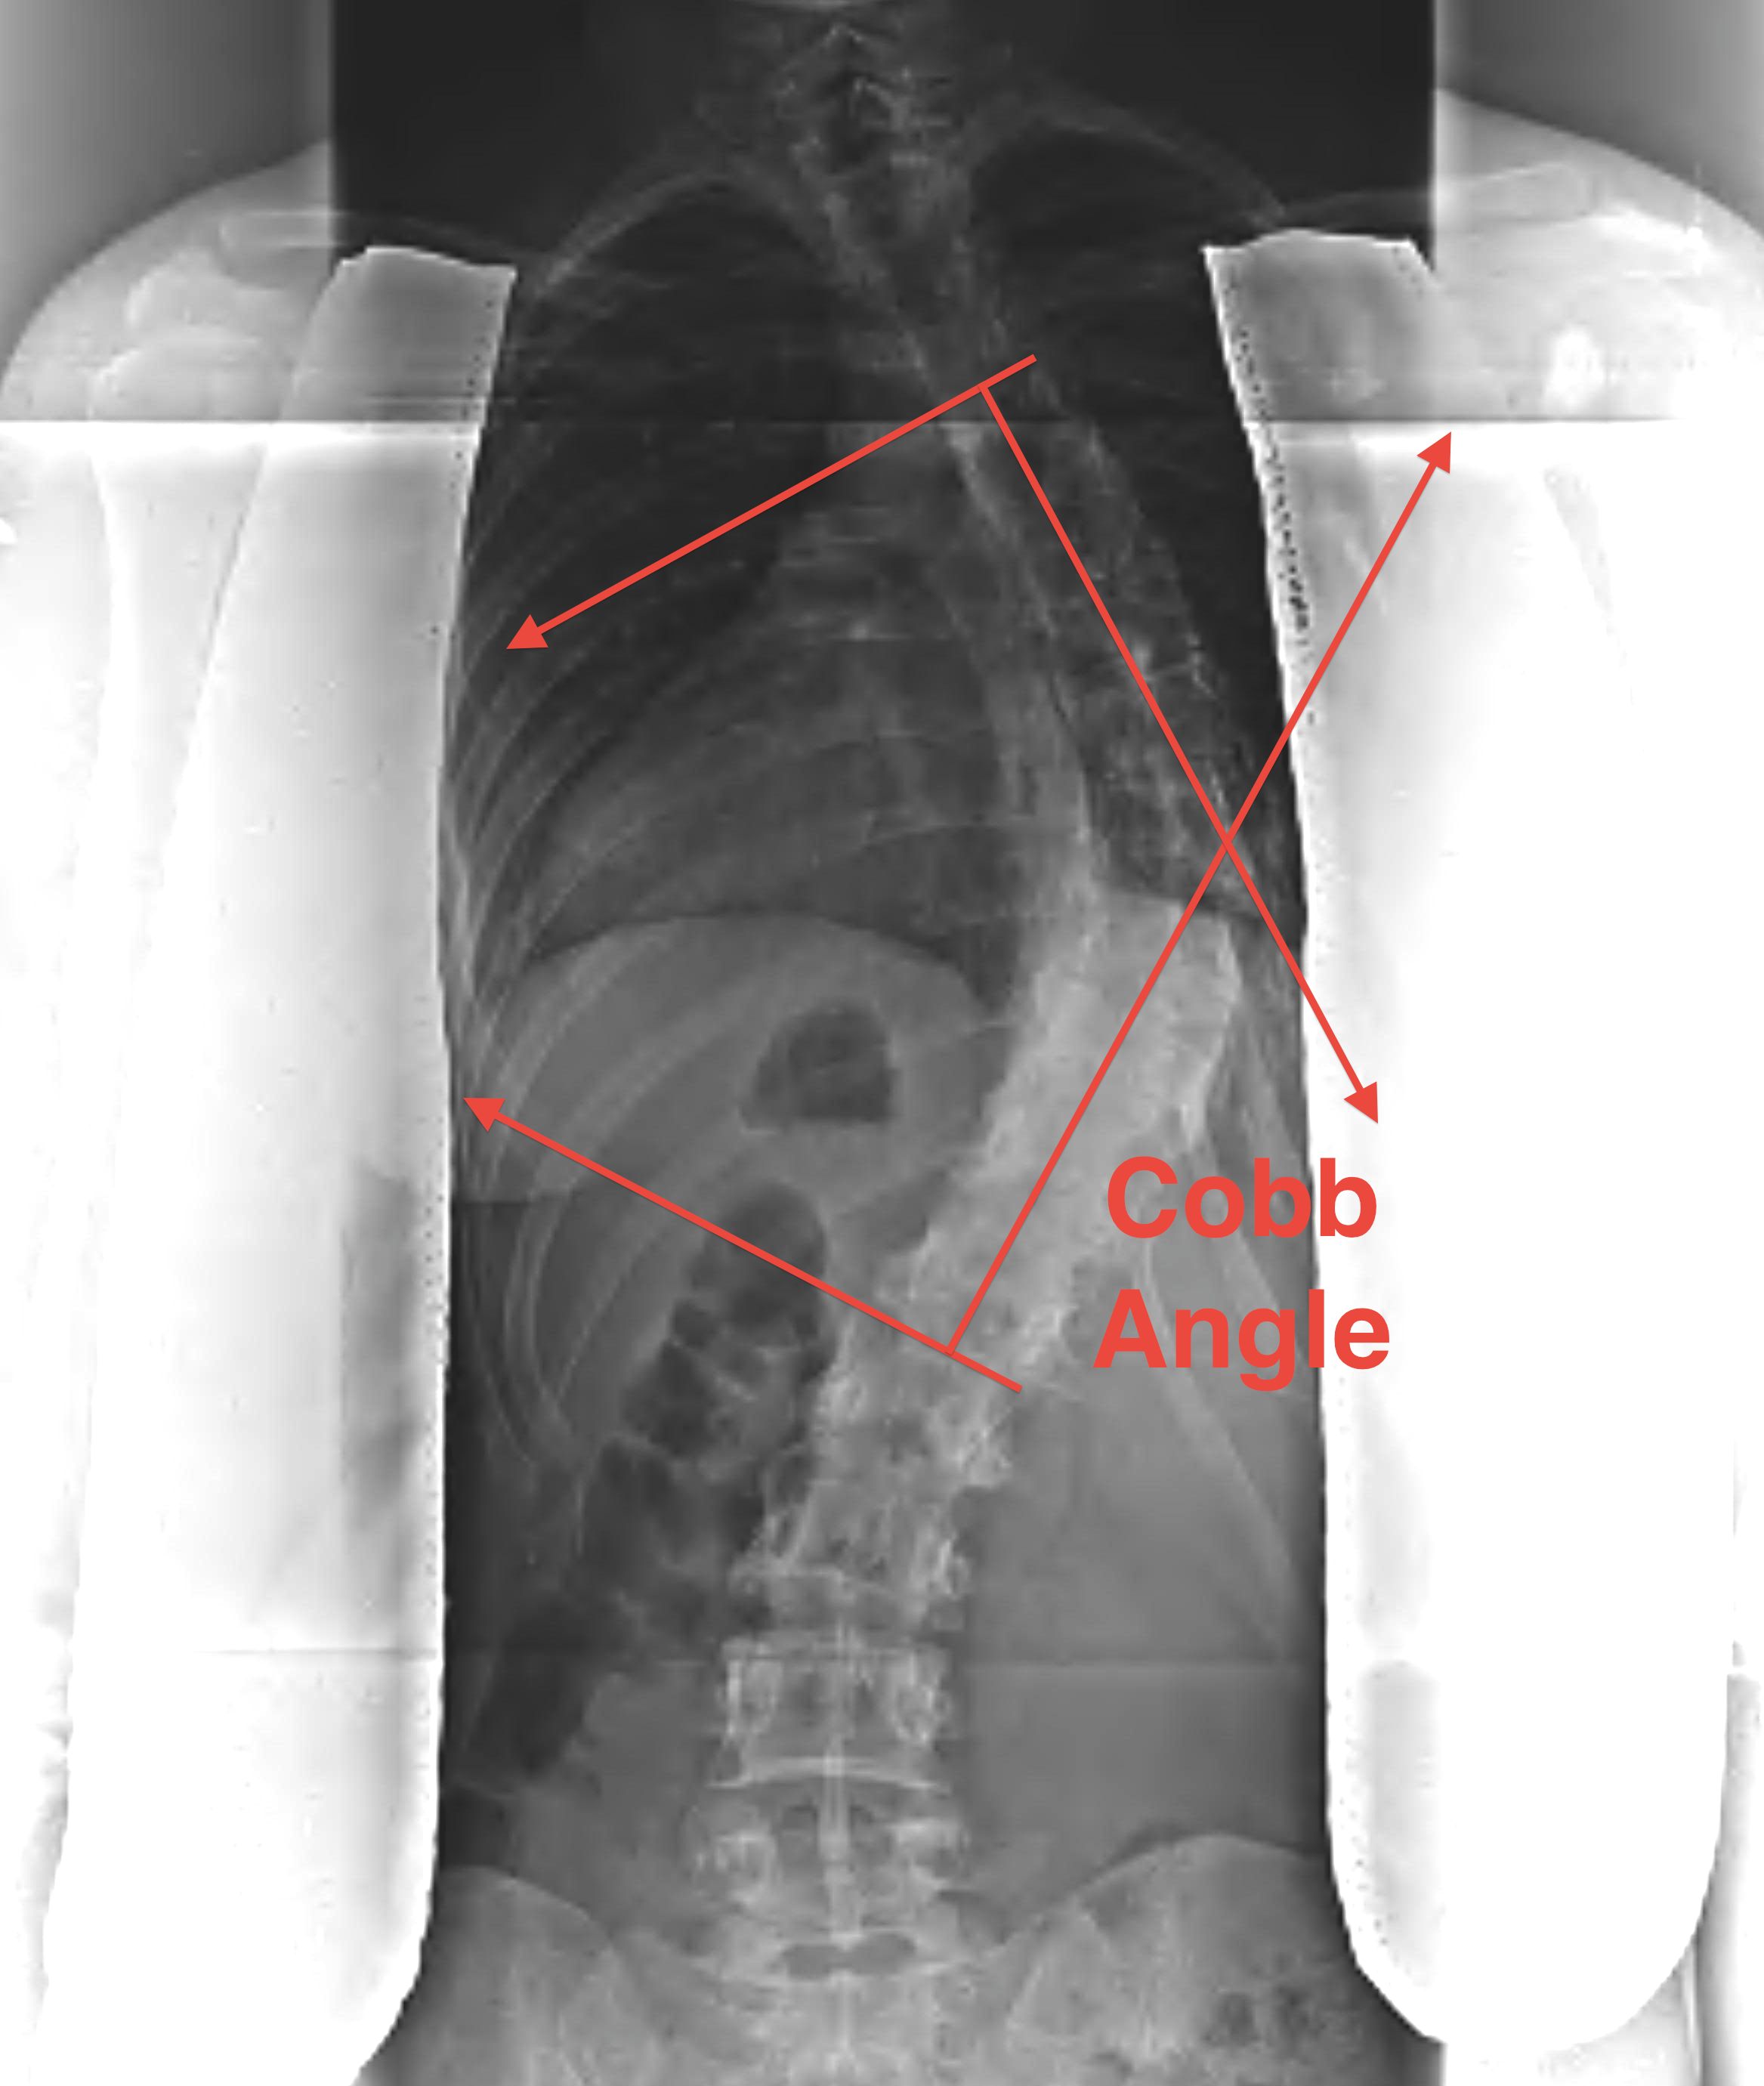

2. Cobb Angle

Detect the end vertebrae where the end plates are last to converge

- line drawn along upper plate of the upper end vertebrae and lower plate of the lower end vertebrae

- perpendiculars to these lines

- intersection angle measured